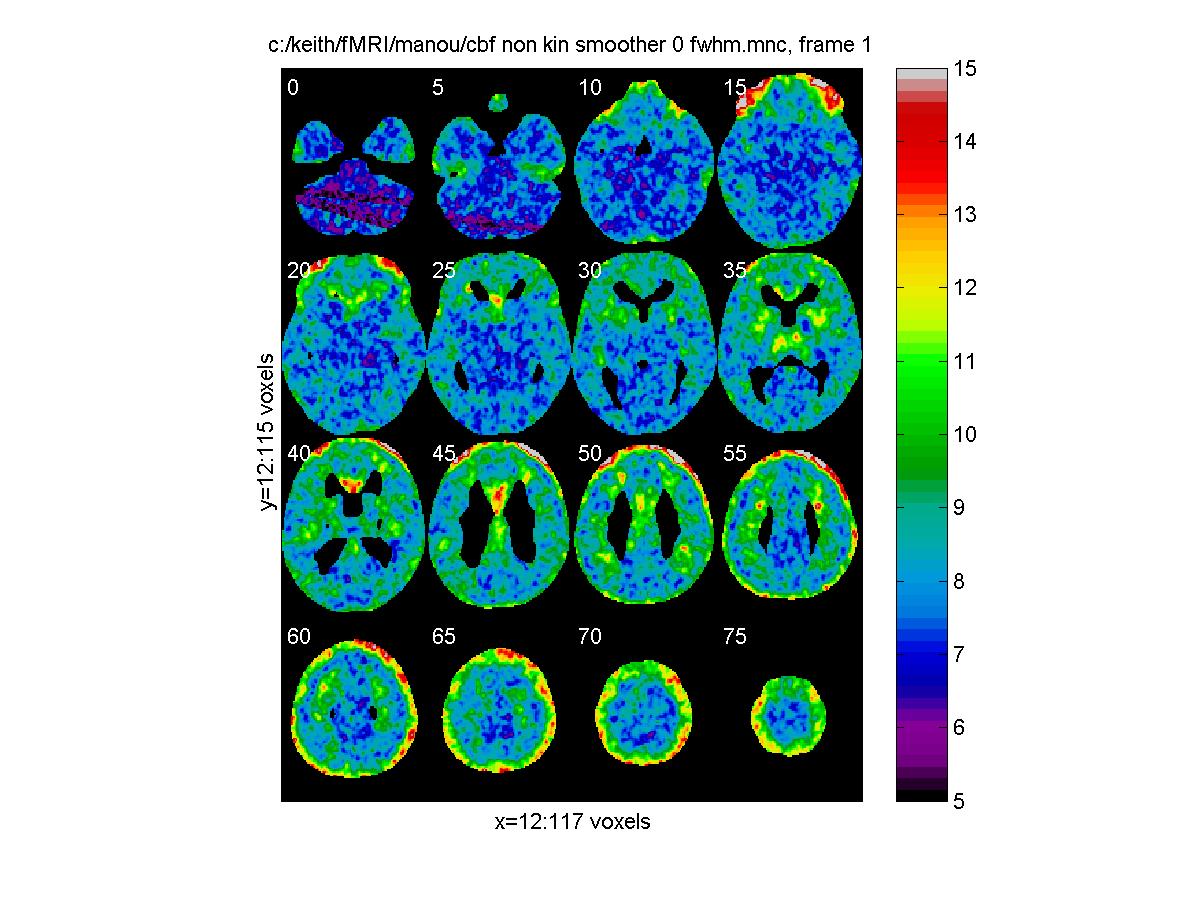

Effective FWHM, in mm:

clf;

view_slices('c:/keith/fMRI/manou/cbf_non_kin_smoother_0_fwhm.mnc',mask,0.65,[0:5:79])

![[Click to enlarge image]](figs_pet_tn/fignormfwhm.jpg)